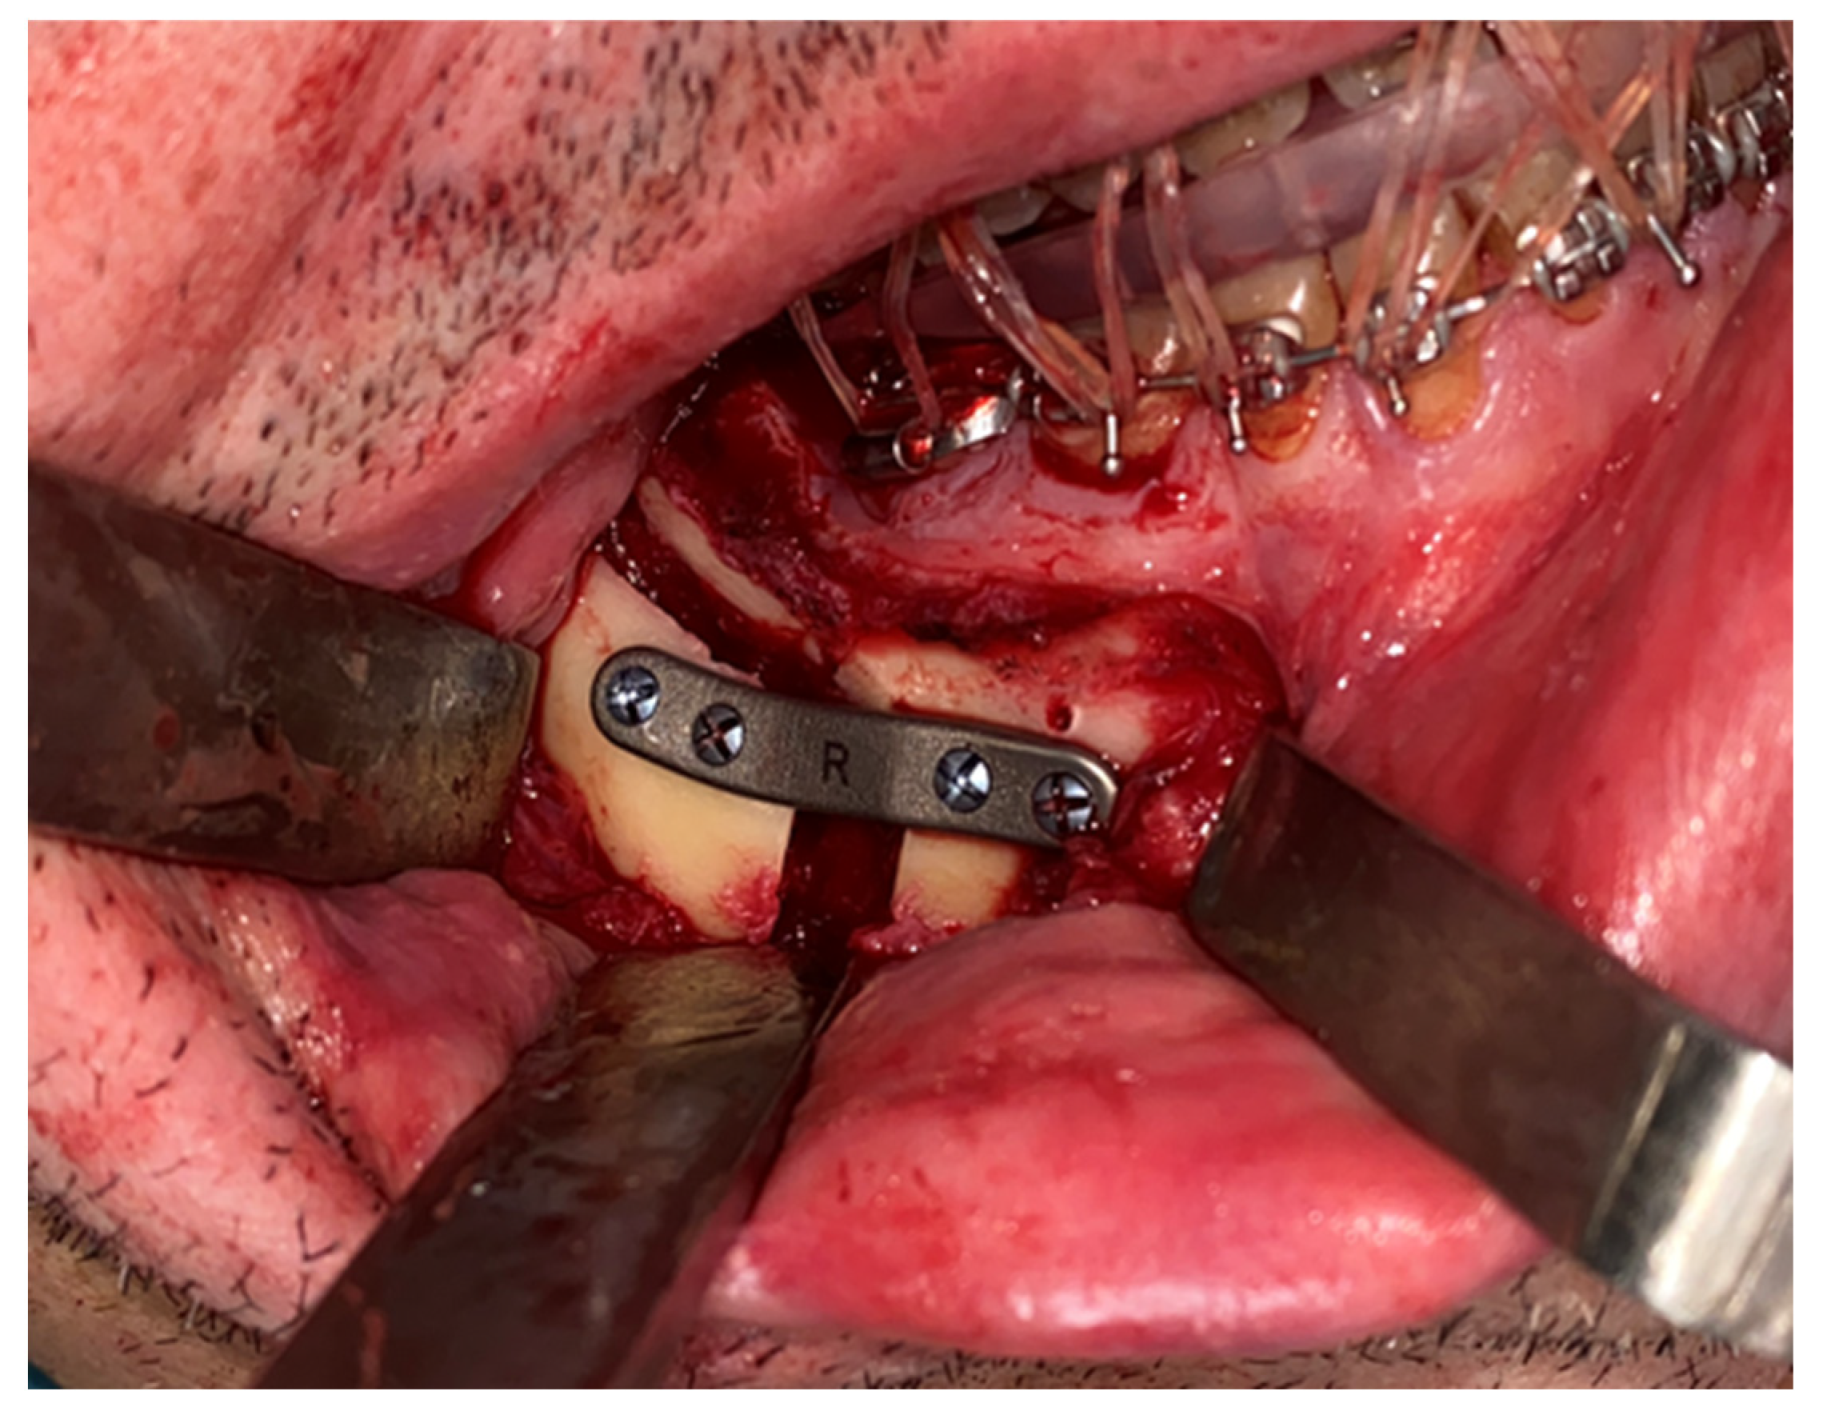

A Le Fort-type osteotomy was performed using a reciprocating saw. The maxilla was positioned according to the preoperative planning and fixed with customized titanium plates (Figure 4). The intermediate splint was used to perform a double check of the patient’s correct position of the maxilla and the dental occlusion.

Figure 3. Step 3. Intraoral approach via vestibular sulcus incision and positioning of the maxillary bone-supported cutting guide, corresponding to the first surgical step following VSP.

Figure 4. Le Fort I osteotomy and fixation of the maxilla using customized plates, verifying transfer of the virtual plan to the surgical site.